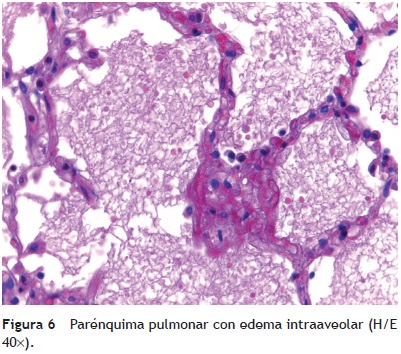

Los pulmones pesaron casi el doble de su peso normal. Macroscópicamente, mostraron áreas de congestión a nivel de los lóbulos basales; histológicamente, la arquitectura está conservada. Lo que llamó la atención fue la presencia de algunas áreas de atelectasia y edema intraalveolar (fig. 6). Había también algunas fibras vegetales en la luz de los bronquiolos; sin embargo, no se encontró reacción tisular y esto sugiere que probablemente la paciente tuvo episodios de broncoaspiración. Se debe recordar que la paciente estaba inmunocomprometida, por lo que no presentó una buena respuesta inflamatoria. Sin embargo, se observaron algunos focos de infiltrado inflamatorio tanto en los alvéolos como en los bronquios y bronquiolos. No había presencia de microorganismos, que se buscaron intencionadamente; entre ellos, Pneumocystis jirovec.